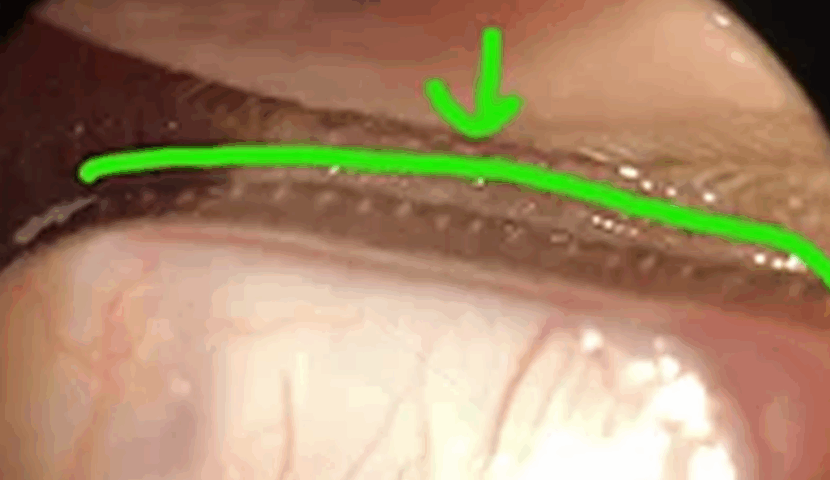

スリットランプ検査にて、マイボーム腺のつまりを確認。圧迫により濁った分泌液を絞り出しました。

| マイボーム腺機能不全と診断。マイボーム腺が目詰まりを起こし、ドライアイ状態になっていました。治療としては眼瞼マッサージや温罨法、ヒアルロン酸点眼などを行います。 完治が目標ではなく、良好な状態を維持することが大切なので、自宅でのケアが大切になります。 |